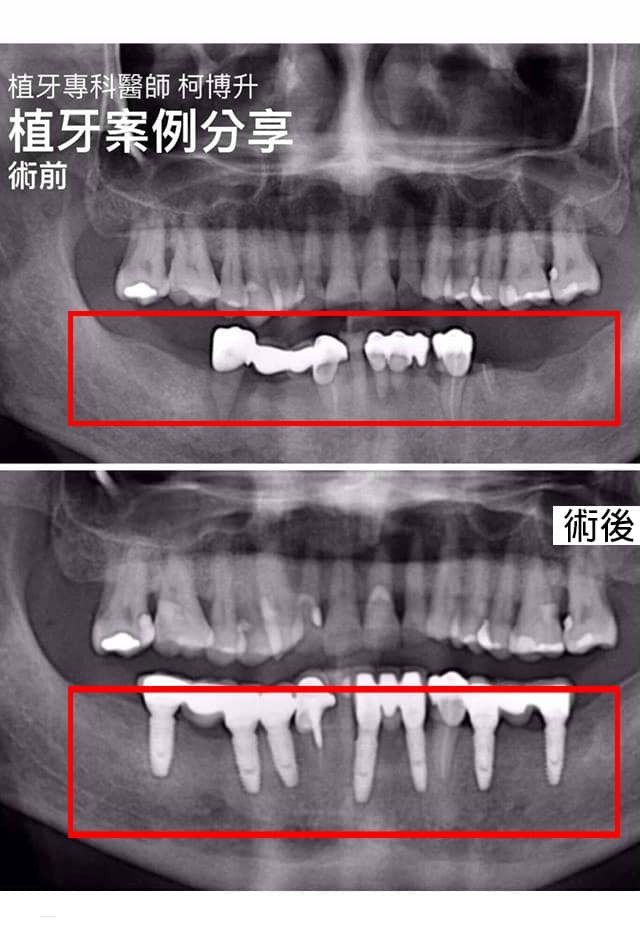

下顎植牙

因缺牙造成咀嚼、發音有問題➡️牙齒歪斜不美觀、蛀牙、咬合不正➡️影響臉型外觀

患者治療後把下顎的長期缺牙補好,從牙齒到臉形美觀都獲得改善